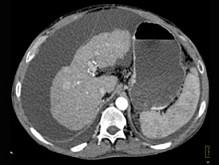

下列图像最可能的诊断是 ( )A.肝脓肿B.肝囊肿C.肝血管瘤D.原发性肝癌E.肝炎肝硬化

问题 下列图像最可能的诊断是 ( )

选项 A.肝脓肿 B.肝囊肿 C.肝血管瘤 D.原发性肝癌 E.肝炎肝硬化

答案 E